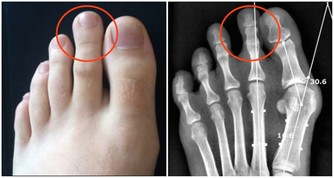

人體外耳道的長度大約有2.5cm~3cm,耳屎只佔外耳道的外三分之一,另外靠近鼓膜的那三分之二並無耳屎佔據。

耳屎呈酸性,它使外耳道保持酸性環境,和耳道壁上的耳毛一起,抵禦外部的細菌侵襲。

「頻繁掏耳朵,將耳屎一掏而盡,等於拆除了耳朵的外部防線,任由細菌侵入耳道和鼓膜,

會引起慢性炎症,出現耳朵疼痛、流膿的症狀,嚴重的甚至會聽力下降。」